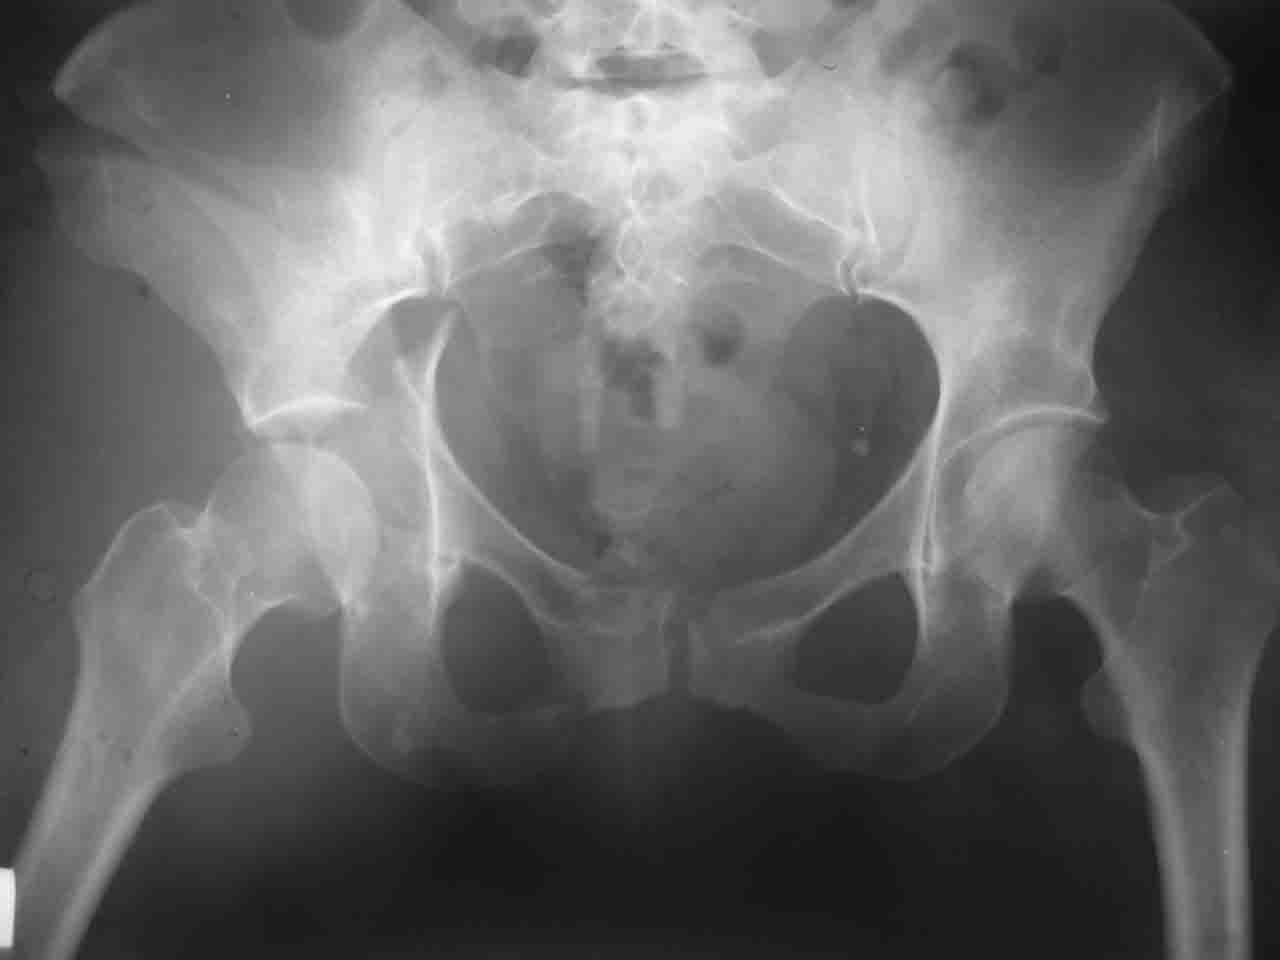

А какой отдел вертлужной впадины более важен передний или задний? Чем был обусловлен выбор доступа к суставу? Проще говоря, почему вы пошли передним доступом на двухколонный перелом? Мне понятны ваши сомнения, когда не удется сделать все что хотелось бы. В данном случае доступ должен быть чрезвертельным боковым (как и советовал Рунков) или двумя доступами.

Логика подсказывает, что все-таки лучше иметь анатомически полноценную впадину, хотя ранее упоминалось состояние вторичной конгруэнтности и одно наблюдение у меня есть, когда у больного с полностью нарушенной анатомией впадины и подвывихом головки бедра кзади и кверху боли отсутствовали при относительно достаточном для стиля жизни больного объёме движений. Но это только одно наблюдение и кроме перелома впадины у этогобольного была и тяжелая ЧМТ в анамнезе. Основываясь на формулировке структуры ацетабулюм Э. Летурнеля - как перевернутой буквы Y, впадина для полноценной функции сустава должна иметь сферичность, соответствующую размеру головки бедра и если один из компонентов в дефиците, то функциональные последствия рано или поздно проявятся.

> передним доступом на двухколонный перелом?

Илеофеморальный доступ не совсем передний и сравнительно с илеоингвинальным, и Кохера-Лангенбека открывает весь наружный таз кроме самых передних отделов лонных костей, фиксацию которых я не ставил в задачу. Обширность диссекции, большая длительность операции и более высокий риск гетерооссификации - отрицательные моменты в обмен на возможность легче ориентироваться.

Вопрос доступа к вертлужной впадине при остеосинтезе задача не простая. Конечно, у Летурнеля и Тайла всё давно описано, нам остается только брать на вооружение. Но сами понимаете, что не бывает двух одинаковых ситуаций, поэтому в каждом случае вопрос решается сугубо индивидуально. Наша главная цель - восстановить анатомию с нанесением минимальной дополнительной травмы тазобедреннному суставу, думаю с этим никто не поспорит. Расширенный илиофеморальный доступ уж слишком травматичен (как сказал один коллега "таз лежит отдельно, больной отдельно").Стоит ли делать из пациента анатомический препарат для того чтобы легче ориентироваться. Да и нужно ли собирать всю "мозаику"? Мы применяли при таких операциях своеобразную операционную хитрость - сначала устраняли грубое смещение крыла под гребнем с фиксацией так называемой "плавающей" пластиной (временно фиксированной на двух винтах)- доступ или продлевали боковой, или делали небольшой дополнительный разрез над гребнем. Это позволяло устранить грубое смещение и захождение отломков тела повздошной кости, что значительно облегчало репозицию и остеосинтез впадины над сводом. Основное внимание конечно же уделяли нагружаемому задне-верхнему отделу. Сообщите ваш адрес, пришлю схемы и рентгенограммы.